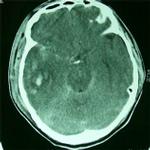

1、顱腦外傷。腦內血腫和腦挫裂傷等。

2、顱內腫瘤和顱內轉移瘤等。

腦包蟲病4、顱內炎症和腦寄生蟲病。各種腦炎、腦膜炎、腦膿腫、腦豕囊蟲病、腦肺吸蟲病、腦包蟲病等。